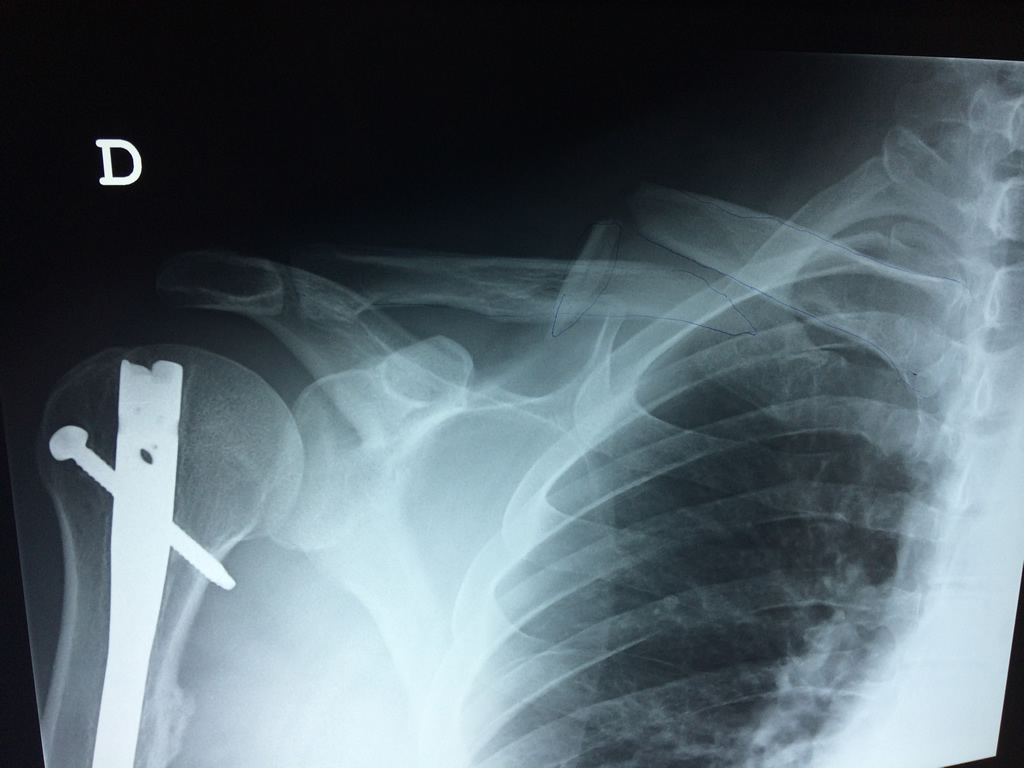

Cirugías de Hombros - Clavícula

La clavícula es un hueso largo, con forma de "S" itálica, situado en la parte anterosuperior del tórax. Junto con la escápula forman la cintura escapular. Se puede palpar por toda su longitud y se extiende del esternón al acromion de la escápula, siguiendo una dirección oblicua lateral y posterior.